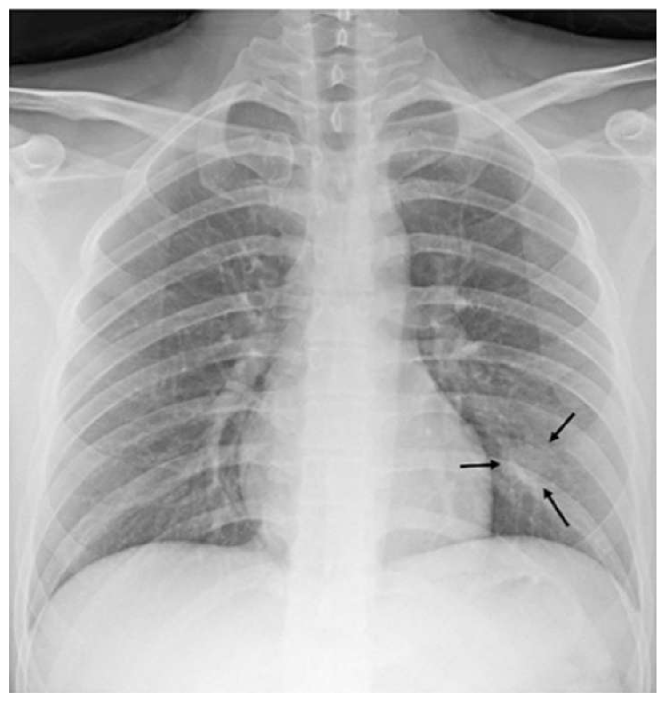

5 Experimental Results

To evaluate the performance, several metrics are considered. Accuracy score is the primary metric used for statistical classification, which is required but inadequate here as we are more interested in efficiently classifying positive samples. Thus, f1-score for the positive class is also measured. The main metric here is visualization heatmaps because the small number of positive samples make the model prone to overfitting by deciding based on the wrong features. The most common manifestations of COVID-19 pneumonia in CXRs are air-space opacities in different forms, such as GGOs or consolidations. Opacities are identified as opaque regions (whiter than usual) in CXRs. They are mostly distinguished as bilateral, involving both lungs, and multifocal opacifications. Rare findings happen in the late stages of disease course, which may include pleural effusion and pneumothorax [29].